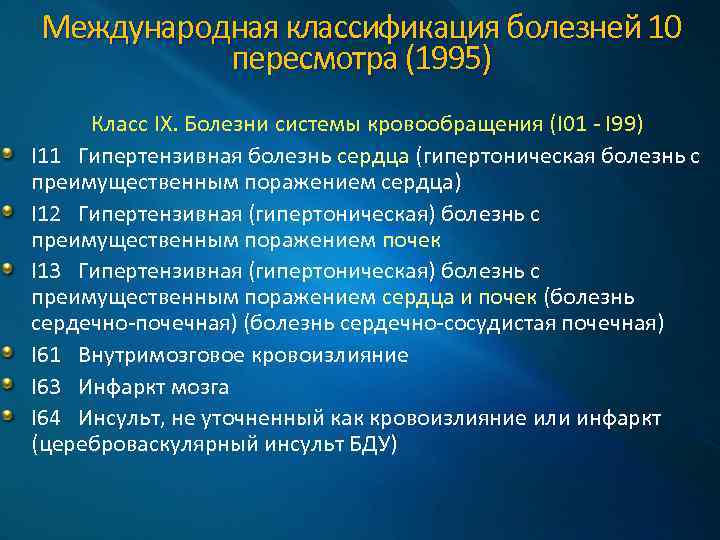

Международная классификация болезней 10 пересмотра (1995) Класс IX. Болезни системы кровообращения (I 01 - I 99) I 11 Гипертензивная болезнь сердца (гипертоническая болезнь с преимущественным поражением сердца) I 12 Гипертензивная (гипертоническая) болезнь с преимущественным поражением почек I 13 Гипертензивная (гипертоническая) болезнь с преимущественным поражением сердца и почек (болезнь сердечно-почечная) (болезнь сердечно-сосудистая почечная) I 61 Внутримозговое кровоизлияние I 63 Инфаркт мозга I 64 Инсульт, не уточненный как кровоизлияние или инфаркт (цереброваскулярный инсульт БДУ)